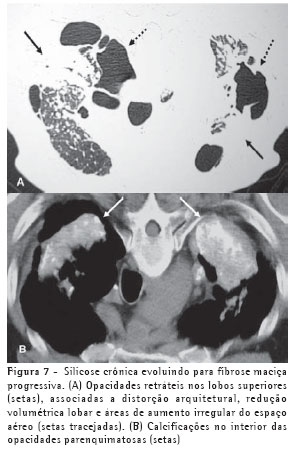

Os achados iniciais na TCAR consistem em micronódulos centrolobulares e subpleurais (Figura 4), menores que 0,5 cm. Com a evolução da doença estes micronódulos tendem à confluência, com formação de nódulos maiores (Figura 5), conglomerados (Figura 6) e, numa fase mais tardia, massas fibróticas, geralmente com calcificações e aumento irregular do espaço aéreo adjacente (Figura 7).(5)

O padrão característico na radiografia é o de pequenos nódulos pulmonares circunscritos, menores que 0,5 cm, geralmente acometendo os campos pulmonares superiores, especialmente as regiões posteriores (Figura 1). Estes nódulos, com o passar dos anos, tendem à coalescência, com formação de grandes opacidades, maiores que 1 cm, o que é conhecido como silicose complicada (Figura 2). Estas podem estar acompanhadas de fibrose pulmonar (fibrose maciça progressiva), com redução volumétrica lobar, distorção arquitetural, retração hilar e fissural e aumento irregular dos espaços aéreos adjacentes.(3)